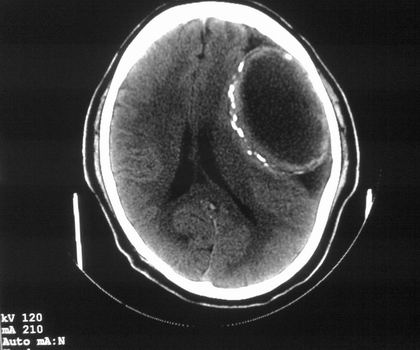

以下是引用影像孺子牛在2008-4-29 21:20:00的发言:[br]首先病变定位在脑外,根据ct密度及mri信号特征考虑慢性硬膜下血肿不连续环形钙化。

以下是引用周战梅在2008-4-29 23:12:00的发言:[br]脑外病变,蛛网膜下腔增宽,囊壁点状、环形钙化,增强扫描呈不均匀环状强化,考虑为囊性脑膜瘤可能性大,慢性脓肿、血肿机化、胆脂瘤不能除外。